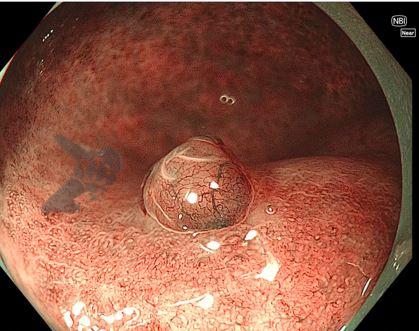

3. EDOF (Extended Depth of Field)

A incorporação do EDOF, ou campo de visão estendida, proporcionou uma melhora significativa na qualidade de imagem. Com o sistema anterior, o Near Focus produzia uma imagem ampliada, porém para atingirmos uma boa resolução, tínhamos que nos aproximar muito do foco de interesse e a imagem ao redor ficava desfocada. Para melhorar nesse aspecto, dois refletores (espelhos) foram colocados na ponta do aparelho, permitindo ver uma área de interesse de perto, porém mantendo a nitidez da área ao redor.